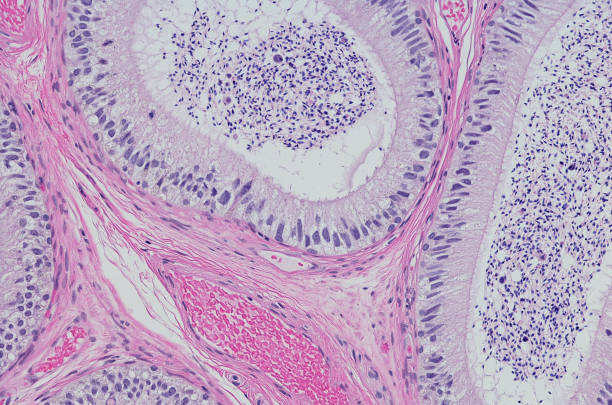

고환암의 진단은 주로 조직검사를 통해 이루어집니다. 이를 통해 암의 종류와 암의 정도를 확인할 수 있습니다. 고환암의 원인은 선천적인 요인과 후천적인 요인으로 구분됩니다.

고환암은 젊은 남성에서 가장 흔하게 발생하는 암 중 하나로, 발병률이 상당히 높습니다. 실제로 15세에서 30대의 젊은 남성에서 발병률이 가장 높습니다. 이 암은 주로 고환 부위에서 발견되며, 증상은 다양할 수 있지만 일반적으로 고환의 크기가 비정상적으로 커지거나 통증을 동반하는 경우에 주로 발견됩니다.